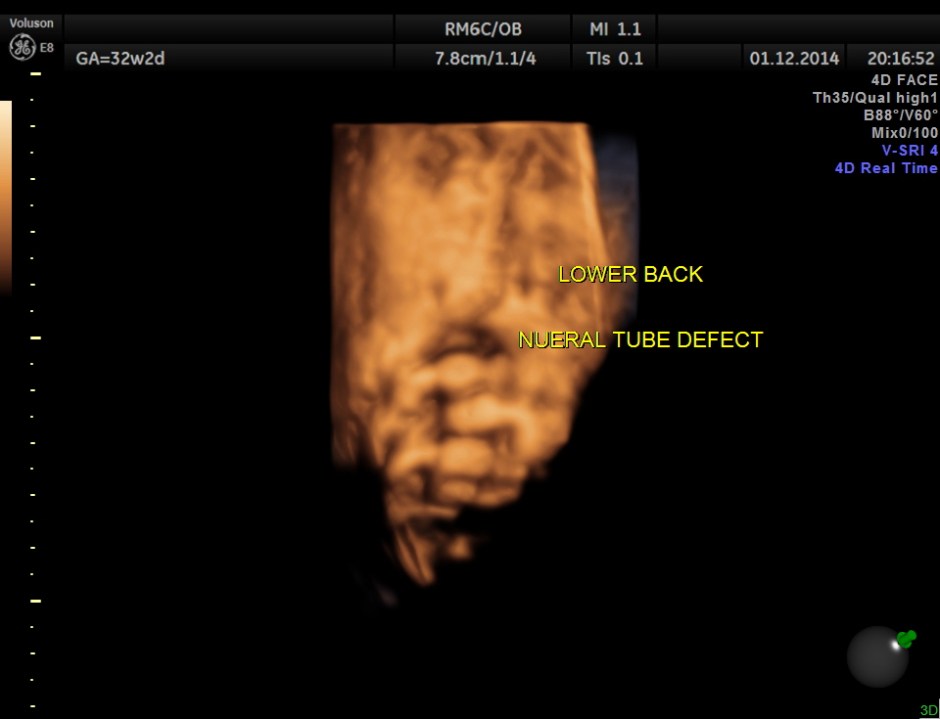

3D view of the same.

Careful examination revealed a neural tube defect with meningo myelocele at the lumbo sacral level.

Spinal deformity was also noted.